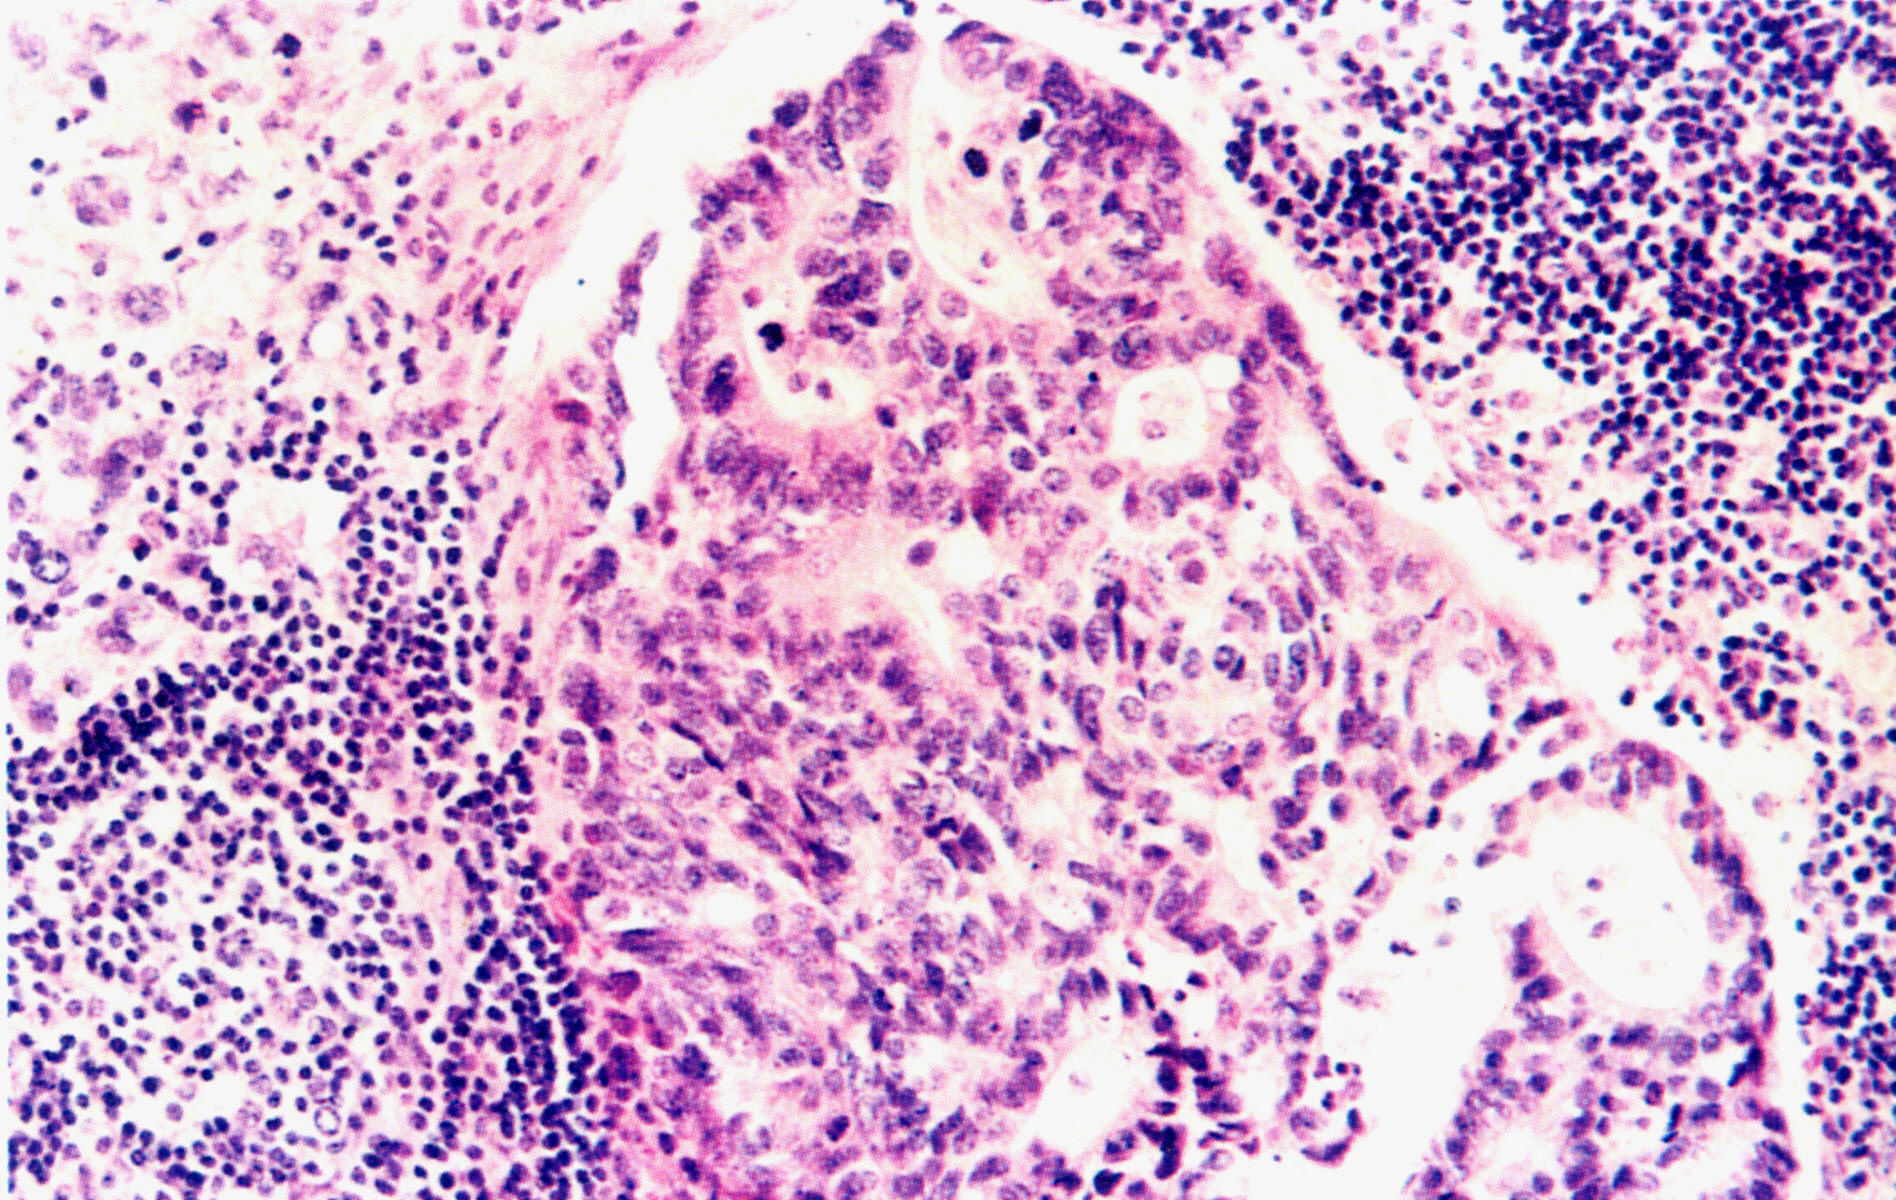

病例分析

临床病理讨论(1)

临床病理讨论(2)

临床病理讨论(3)

临床病理讨论(4)

临床病理讨论(5)